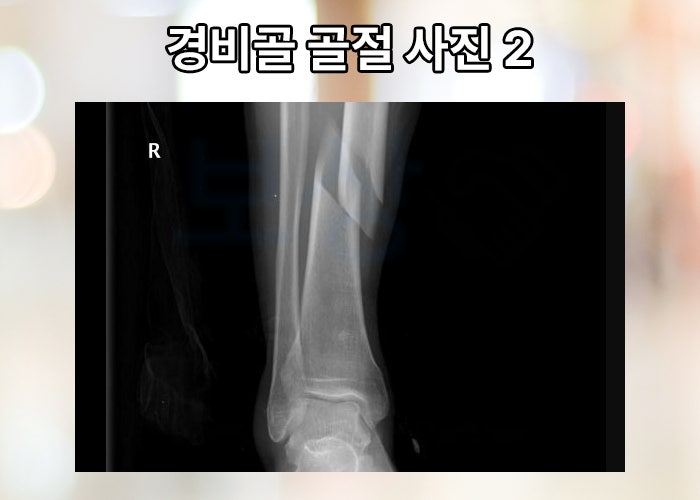

눈이 얼어있던 곳에 꽈당

발판에서 미끄러짐 사고를 당한 의뢰인. 사고를 당한 의뢰인은 사고 초기 다리의 극심한 통증을 호소하시며 응급실로 내원하셨다고 합니다. 발목 골절이 발생하게 되면 심하지 않는 경우라면 석고 고정하는 보존적 치료 하지만 향후 불안정성이나 관절면의 골절이 의심되는 경우 수술적 치료를 시행합니다.

하지만 문제는 회복을 하는 과정 중 환자마다 다양한 후유증이 발생할 수 있습니다. 통증이나 붓기 뿐만이 아니라 심지어 신경 손상이 발생하거나 외상성 관절염, 운동 범위의 제한 등의 후유증이 발생할 수 있죠.

수술적 치료를 한 후에도 움직임이 예전처럼 자유롭지 않다고 느끼셨고 보상파트너 손해사정팀의 무료 상담을 받아보시게 되었습니다. 기본적으로 보험 가입된 상황이나 현재 장해 상태, 치료 과정등에 대해 대화하며 기본 상담을 진행해 드렸습니다.